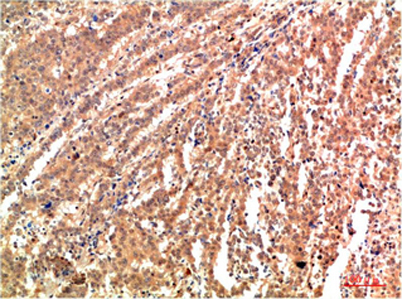

| Dilutions: | WB 1:500-2000,IHC-p 1:50-300 |

| Background: | The protein encoded by this gene is a member of the MAP kinase family. MAP kinases act as an integration point for multiple biochemical signals, and are involved in a wide variety of cellular processes such as proliferation, differentiation, transcription regulation and development. This kinase targets specific transcription factors, and thus mediates immediate-early gene expression in response to various cell stimuli. It is most closely related to MAPK8, both of which are involved in UV radiation induced apoptosis, thought to be related to the cytochrome c-mediated cell death pathway. This gene and MAPK8 are also known as c-Jun N-terminal kinases. This kinase blocks the ubiquitination of tumor suppressor p53, and thus it increases the stability of p53 in nonstressed cells. Studies of this gene's mouse counterpart suggest a key role in T-cell differentiation. Several alternative |